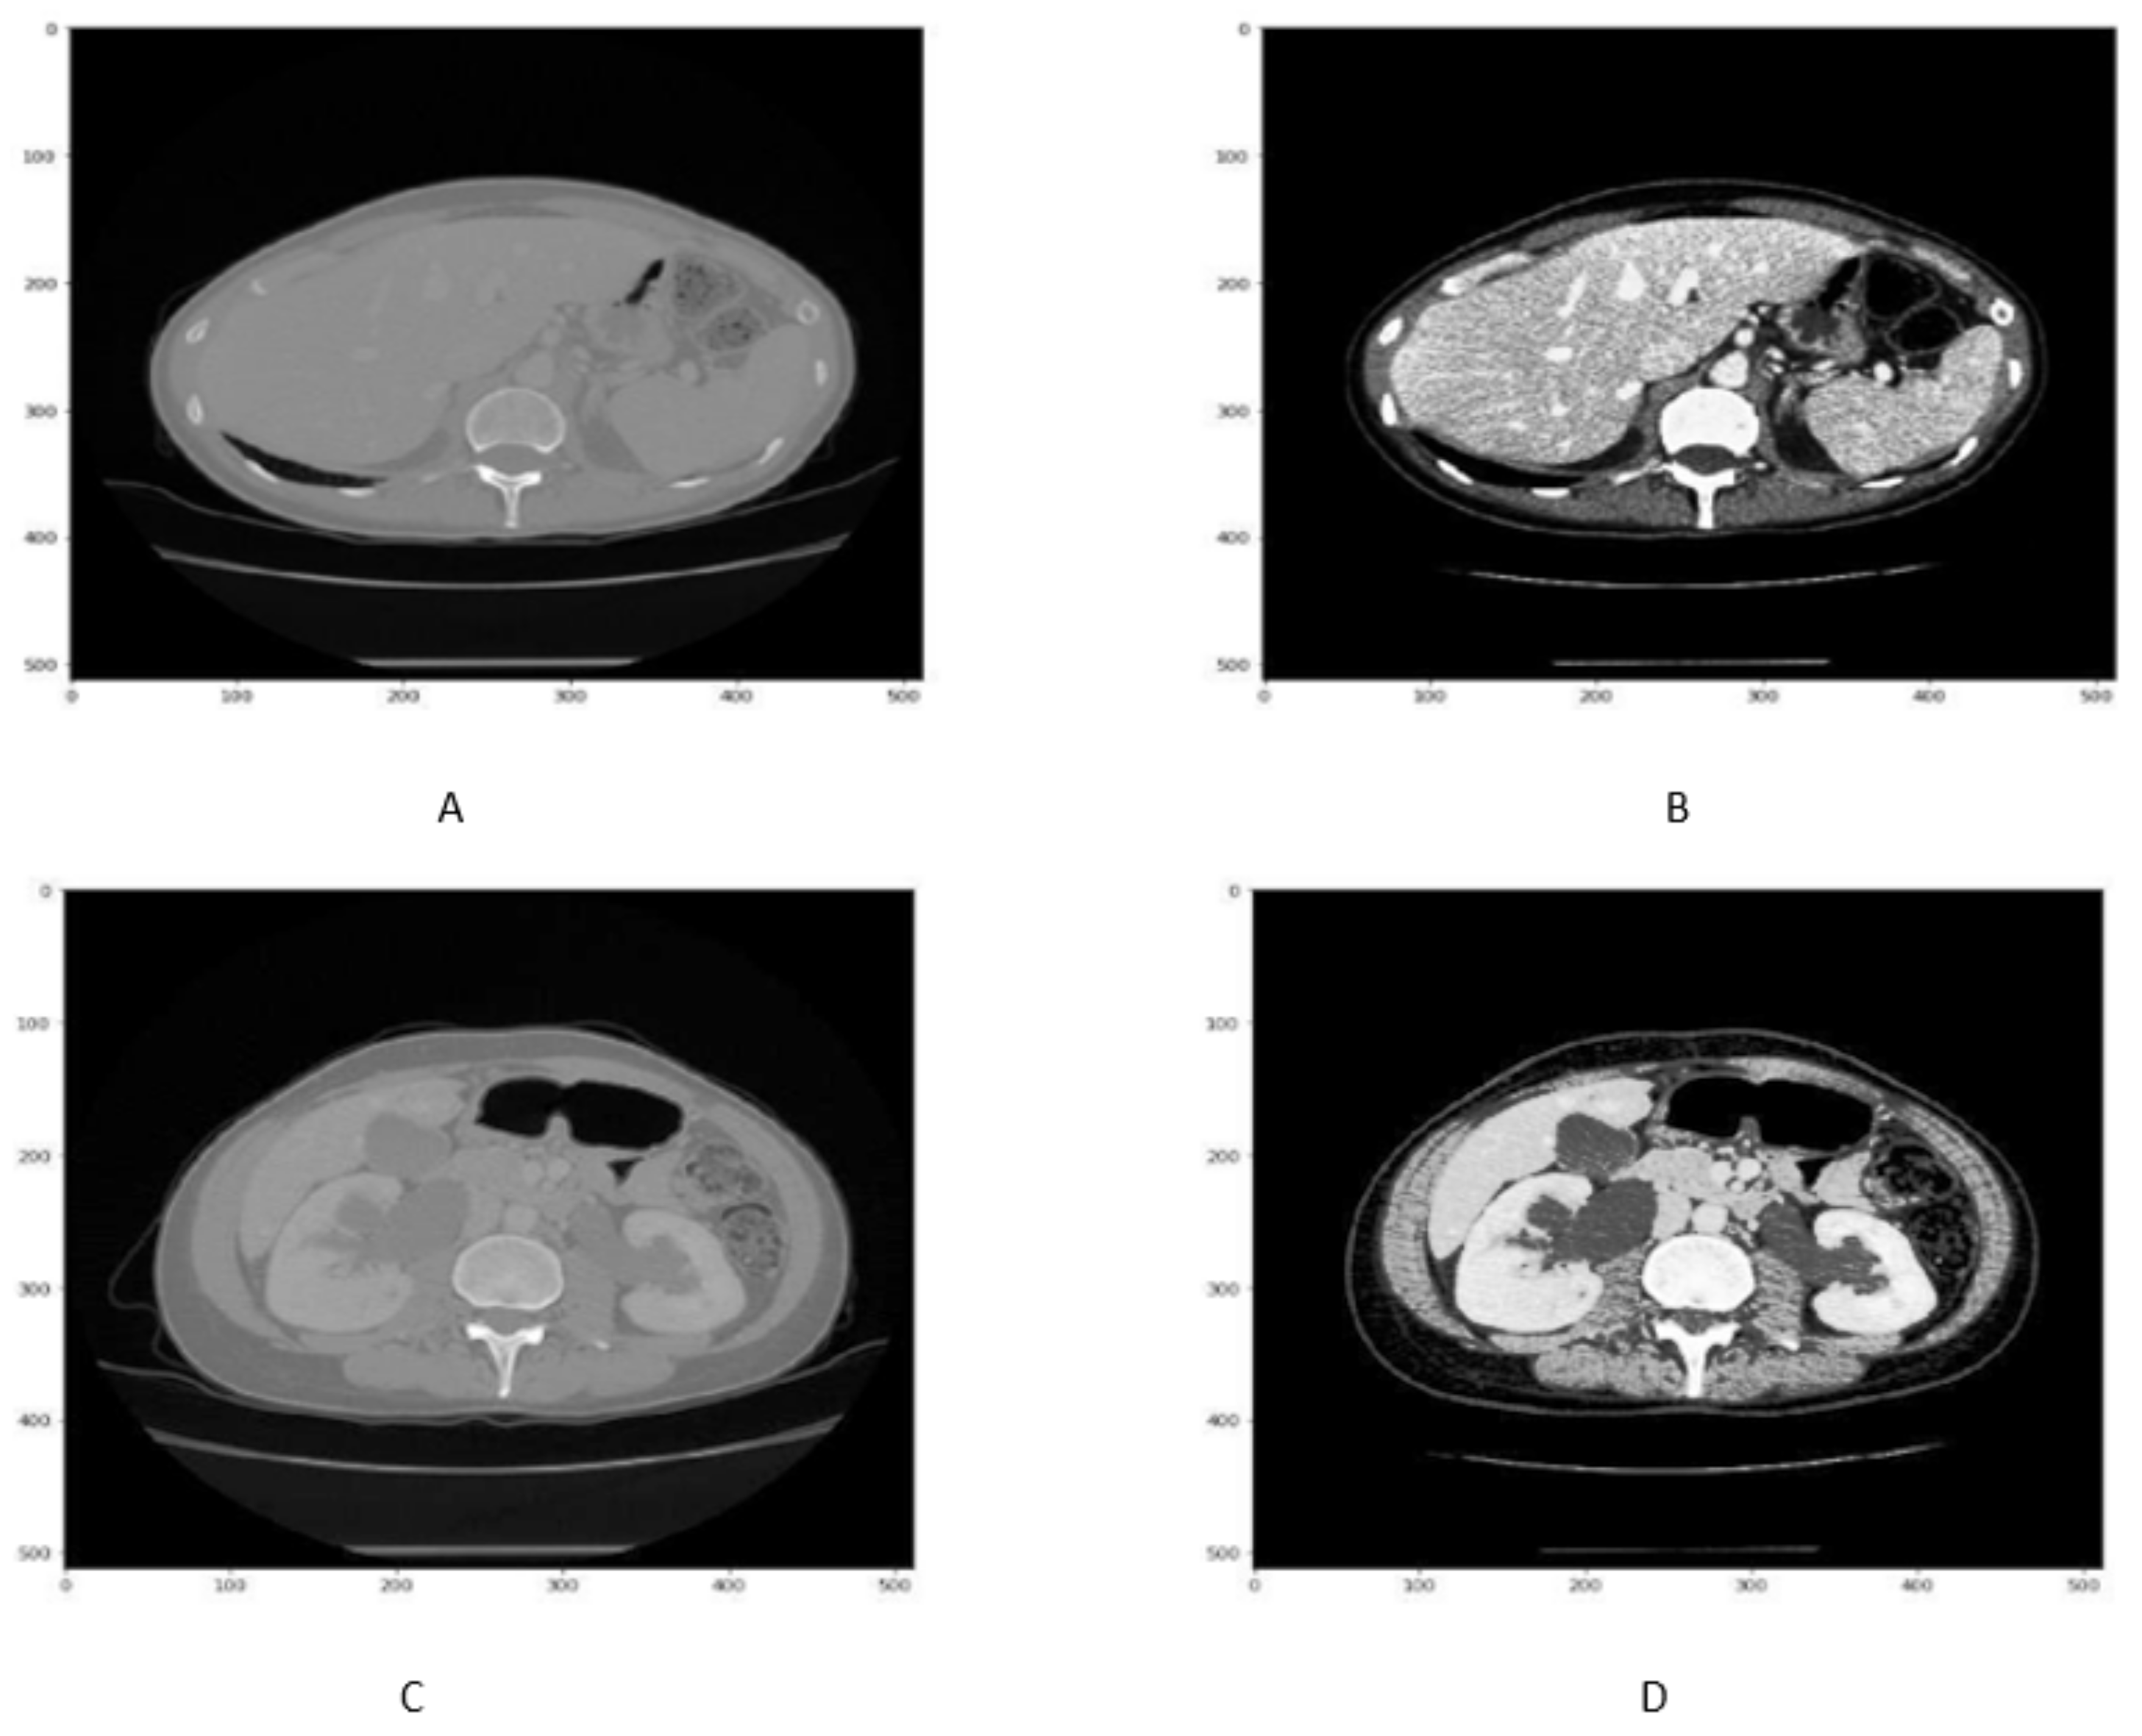

Although HU windowing provides good visualization of organs, it was still difficult to differentiate between the liver and adjacent tissues. Therefore, histogram equalization was applied to the image obtained after window processing and then normalized in the range of [0, 1] as shown in Figure 3. It can be seen that as compared with Figure 2A,B, the organs boundaries are more evident in Figure 3C,D after histogram equalization.

Figure 3.

Figure shows that the CT slice (A,B) before histogram equalization, While CT slice (C,D) after histogram equalization.